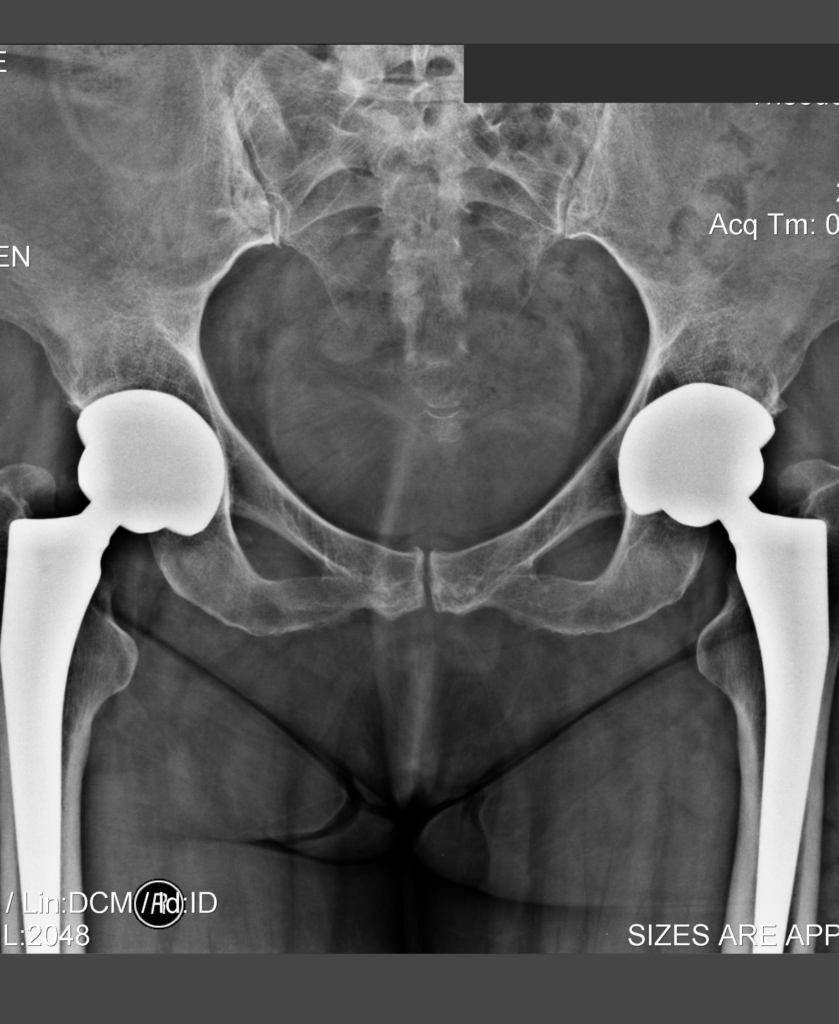

Ακτινογραφίες ασθενή ΜΕΤΑ από επέμβαση αμφοτερόπλευρης αρθροπλαστικής ισχίων που πραγματοποιήθηκε προ 10ετίας